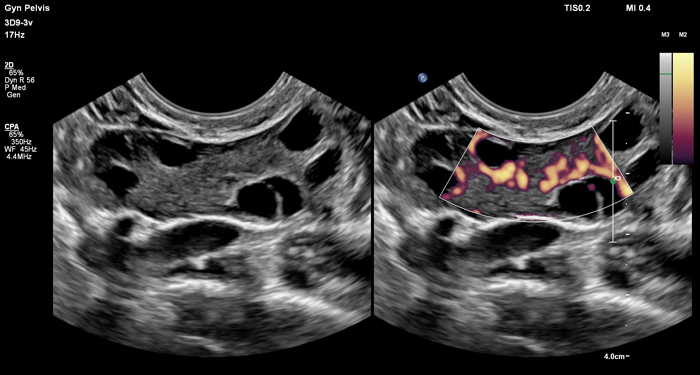

At the touch of a button, the new MaxVue high-definition display brings extraordinary visualisation of anatomy with 1,179,648 additional image pixels compared to a standard 4:3 display format mode. MaxVue enhances ultrasound viewing during interventional procedures and provides 38% more viewing area to optimise the display of dual, side/side, biplane, and scrolling imaging modes.

MaxVue offers a 38% greater viewing area.